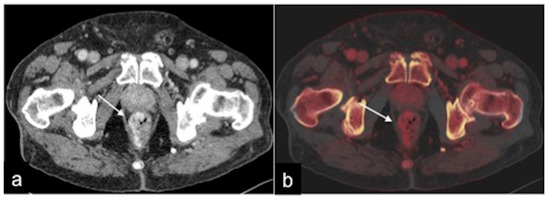

| Meckel’s Diverticulum (Figure 30) | Asymptomatic or, rarely, massive gastrointestinal bleeding. | A diverticulum with fluid or air content originating from the antimesenteric side of the distal ileum. |

| Aorto-Enteric Fistula (Figure 31) | Bleeding in a patient with a history of surgery for aortic aneurysm. | A connection between the aorta and the intestinal lumen. Absence of adipose cleavage planes. |